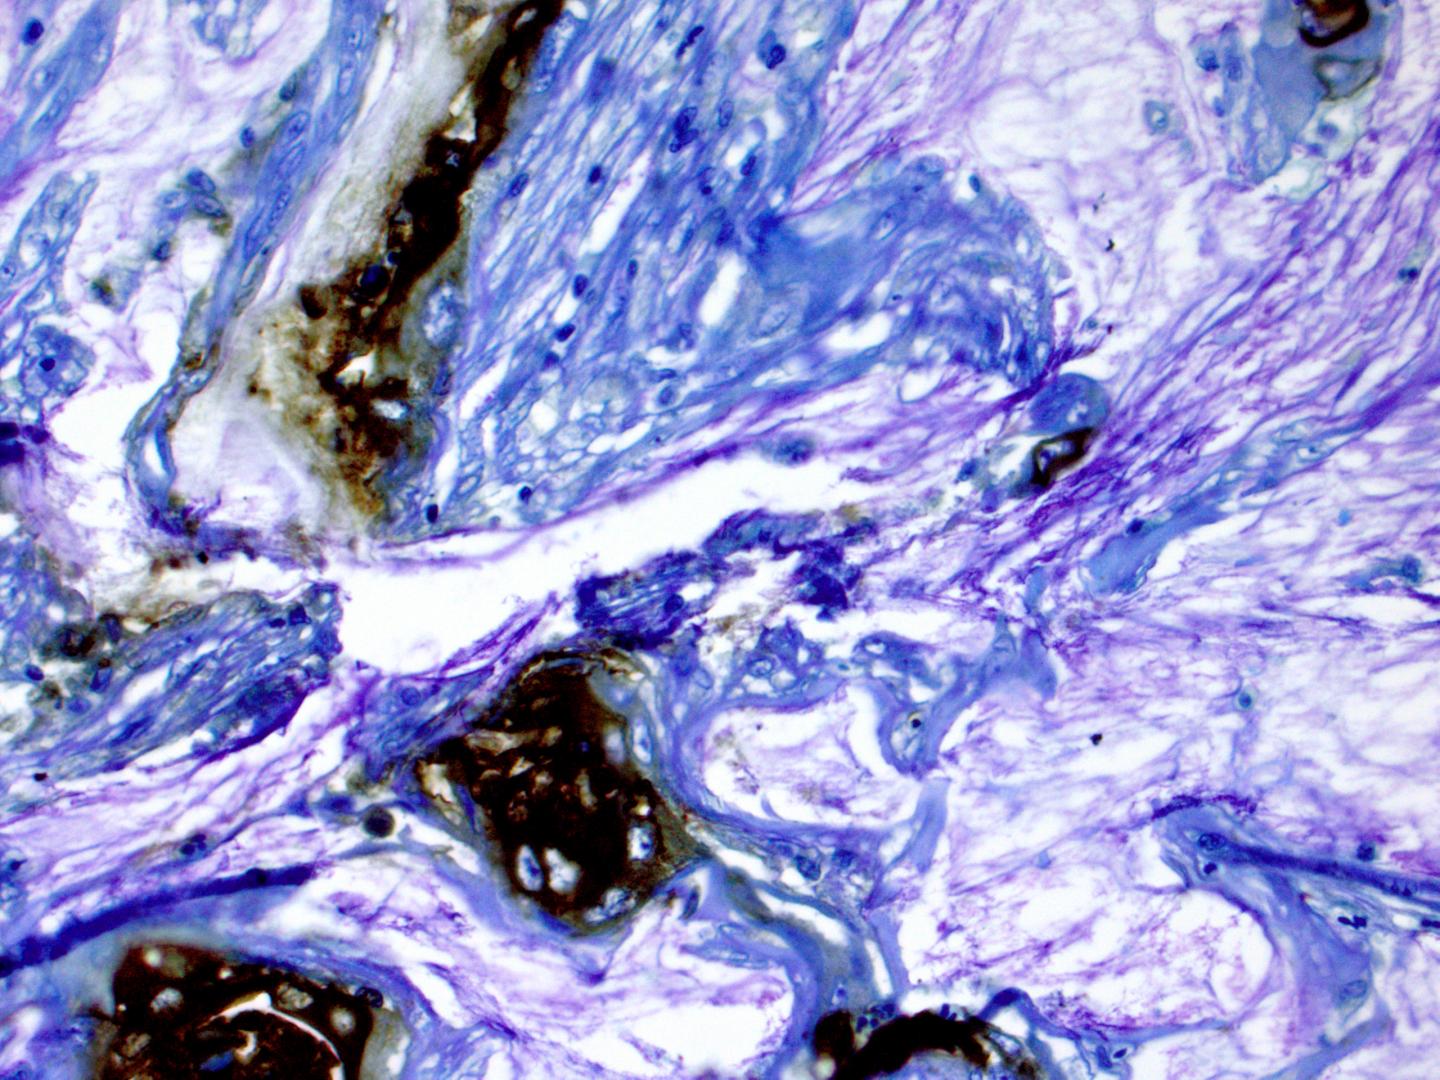

Now, a multicenter team led by investigators at Washington University School of Medicine in St. Louis has taken a big step toward identifying the cysts likely to become cancerous. Testing fluid from cysts for a biomarker -- an antibody called mAb Das-1 -- the researchers were able to identify pancreatic cysts likely to become cancerous with 95 percent accuracy. Current clinical guidelines are only about 74 percent accurate.

The research team collected fluid from the cysts of 169 patients who had surgery to remove the pancreatic cysts. The researchers analyzed the fluid, using a test to detect the Das-1 antibody biomarker. In previous research, the biomarker had been correlated with pancreatic cysts at high risk to become cancerous. In the new study, the researchers found that the biomarker was more accurate than any current method at predicting cancer risk in these patients with pancreatic cysts.